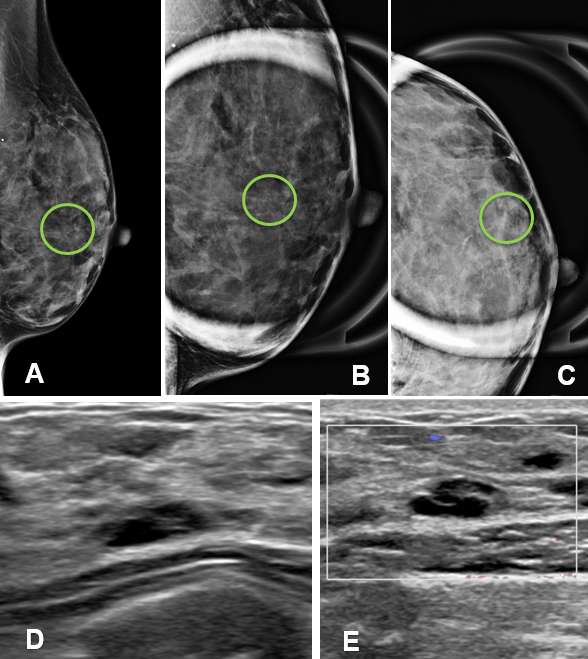

Case: Cysts figure 4

Figure 4A demonstrates a group of microcalcifications in the left breast. Additional views in Figure 4B in ML spot compression which show a curvilinear distribution of the calcifications that subsequently change orientation and become more “smudged” on CC spot compression views in Figure 4C due to the calcifications being viewed en fosse. This phenomenon demonstrates layering calcifications that a typical of benign, milk of calcium sediment. Additional evaluation with ultrasound on the same patient revealed a simple clustered microcyst in the region of interest as seen in Figures 4D and 4E. Note the calcifications are not always visible on ultrasound.